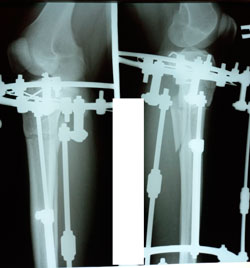

Исходник - 33 года.

Дата операции - 25.01.2021